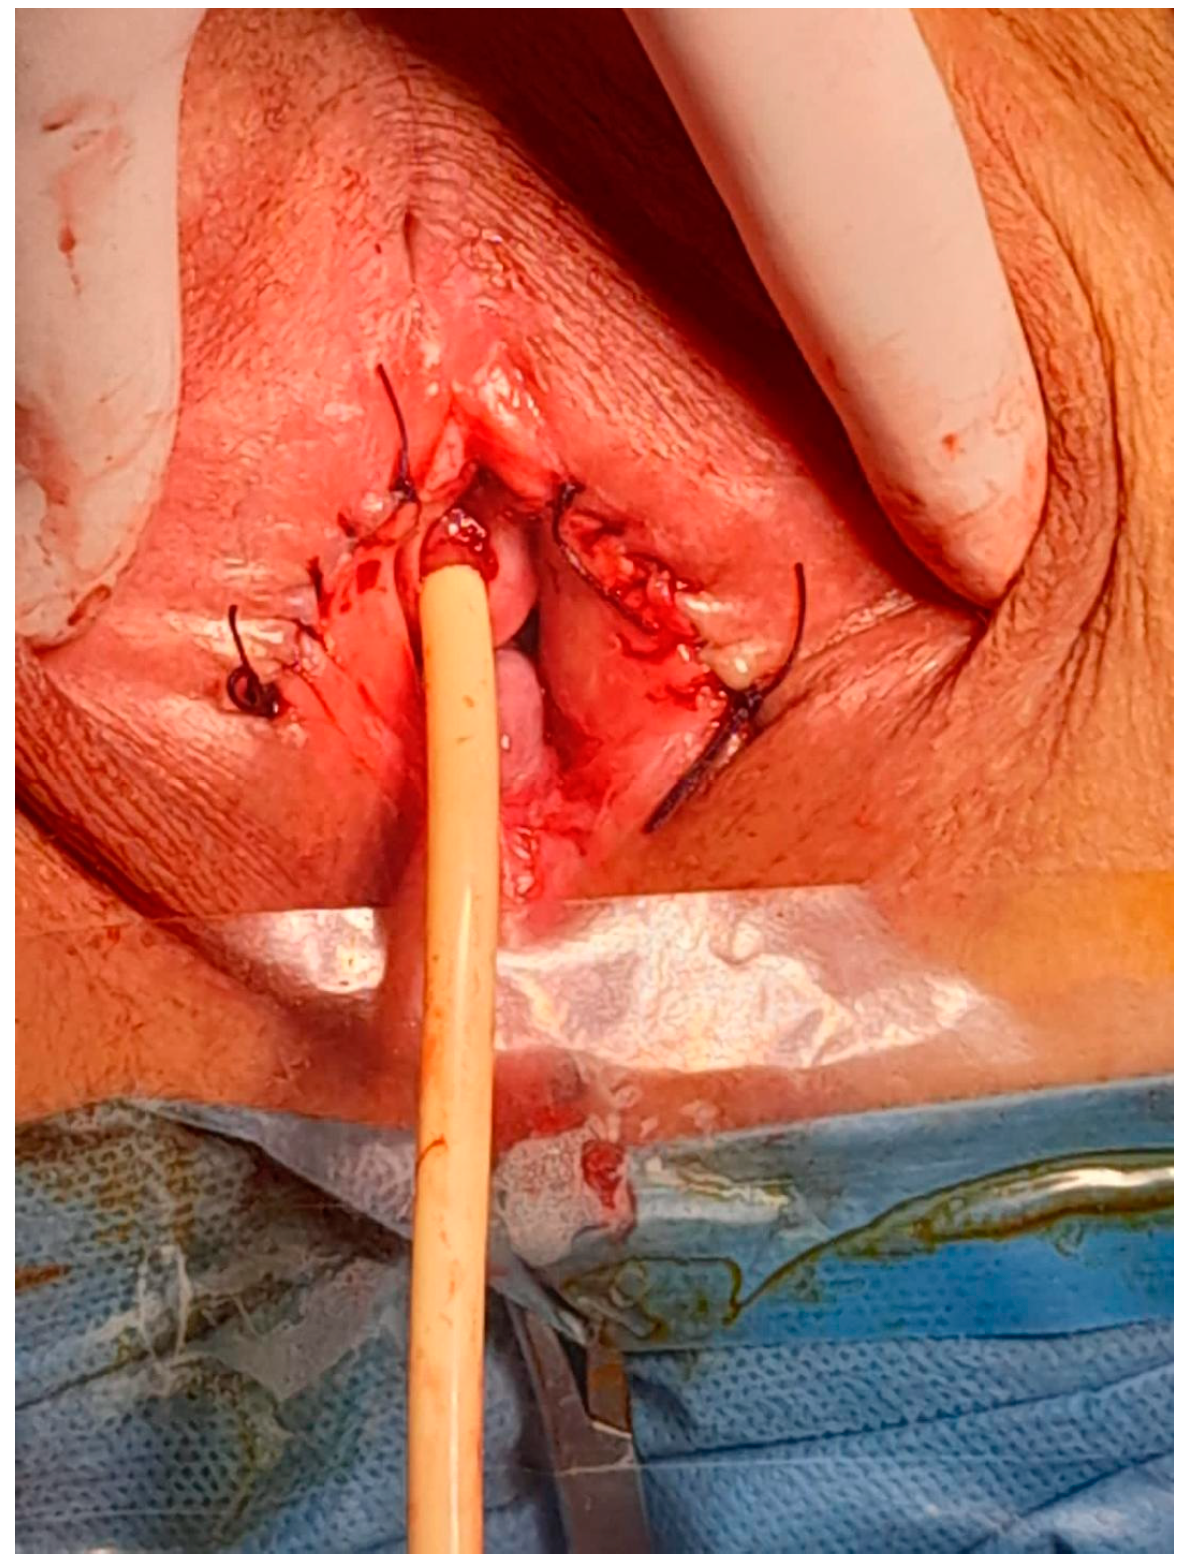

After obtaining informed consent, the patient was taken to the operating room. Under spinal anesthesia, she was positioned in lithotomy and prepared for the procedure. A small opening in the fused labia majora was elevated, and a midline vertical incision was made upward from the posterior orifice using a buttoned stiletto, clearly exposing the vaginal introitus up to the external urethral orifice (Figure 3, Figure 4 and Figure 5). The adhesion between the labia minora and the corresponding labia majora resulted in the resorption, shrinkage, or complete disappearance of the labia minora (Figure 5). The vaginal epithelium appeared to be atrophic and inflamed as a secondary effect. A 14F catheter was used to drain the bladder, and urinalysis revealed a urinary tract infection caused by Escherichia coli.

The mucosa and the skin were sutured with surjet 2-0 Vicryl (Figure 6). We fixed both major labia on the perineal skin to keep the introitus open (Figure 7).

Figure 3. Introduction of a buttoned stiletto into the small opening in the fused labia majora.